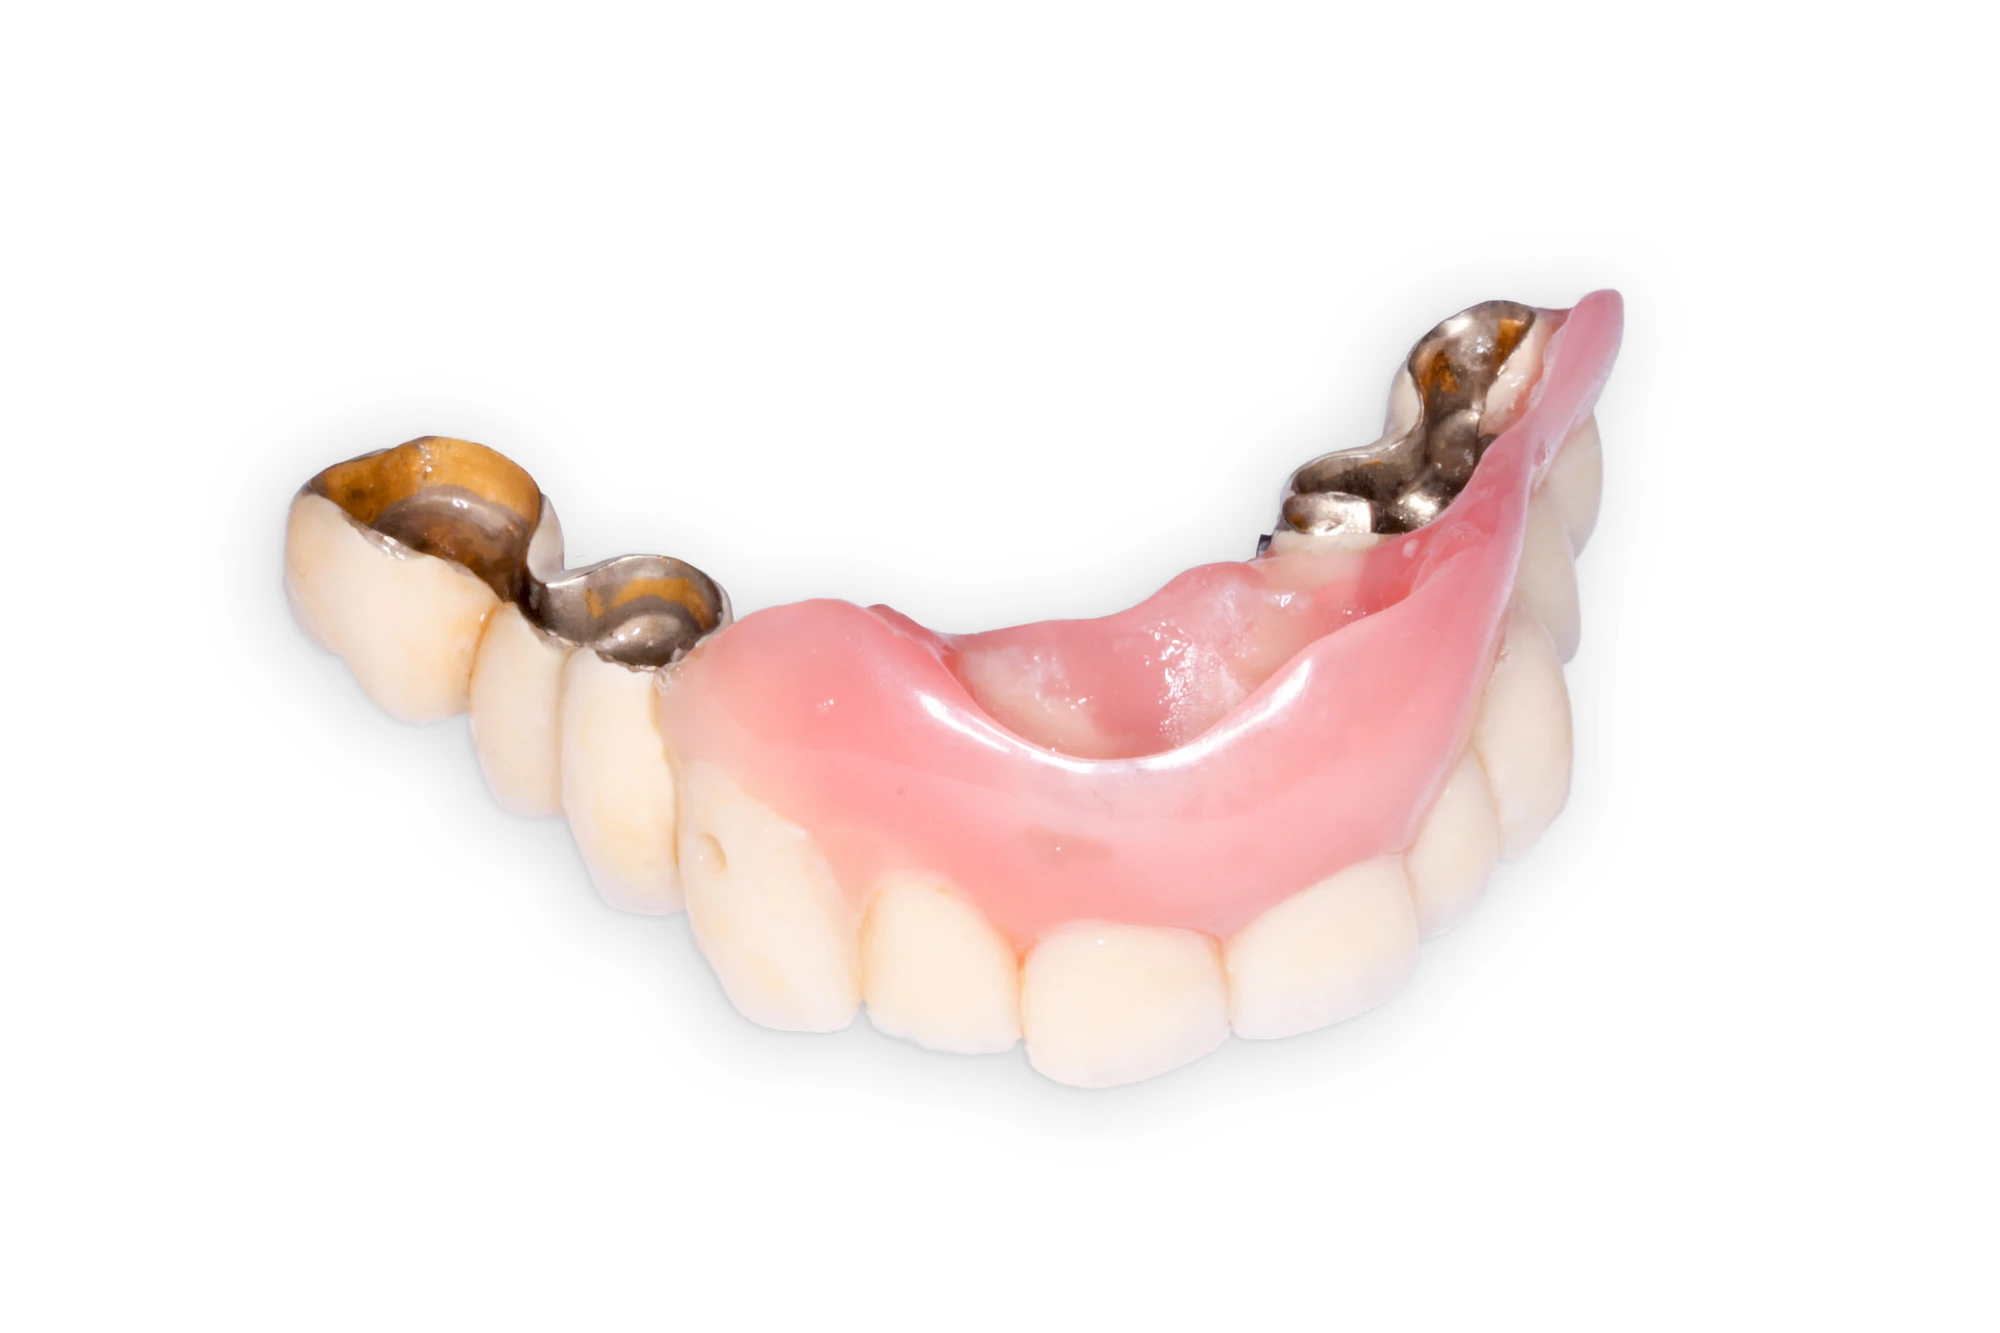

Heute werden in Deutschland Menschen mit Lippen-Kiefer-Gaumenspalten bereits ab Geburt von Experten verschiedener Fachrichtungen (Mund-Kiefer-Gesichtschirurgen, Kieferorthopäden, Logopäden) betreut, damit entsprechende Korrekturen schon frühzeitig erfolgen können. Gerade jedoch bei älteren Menschen ist dies nicht immer geschehen. Diese Menschen tragen häufig technisch aufwendige Zahnprothesen.